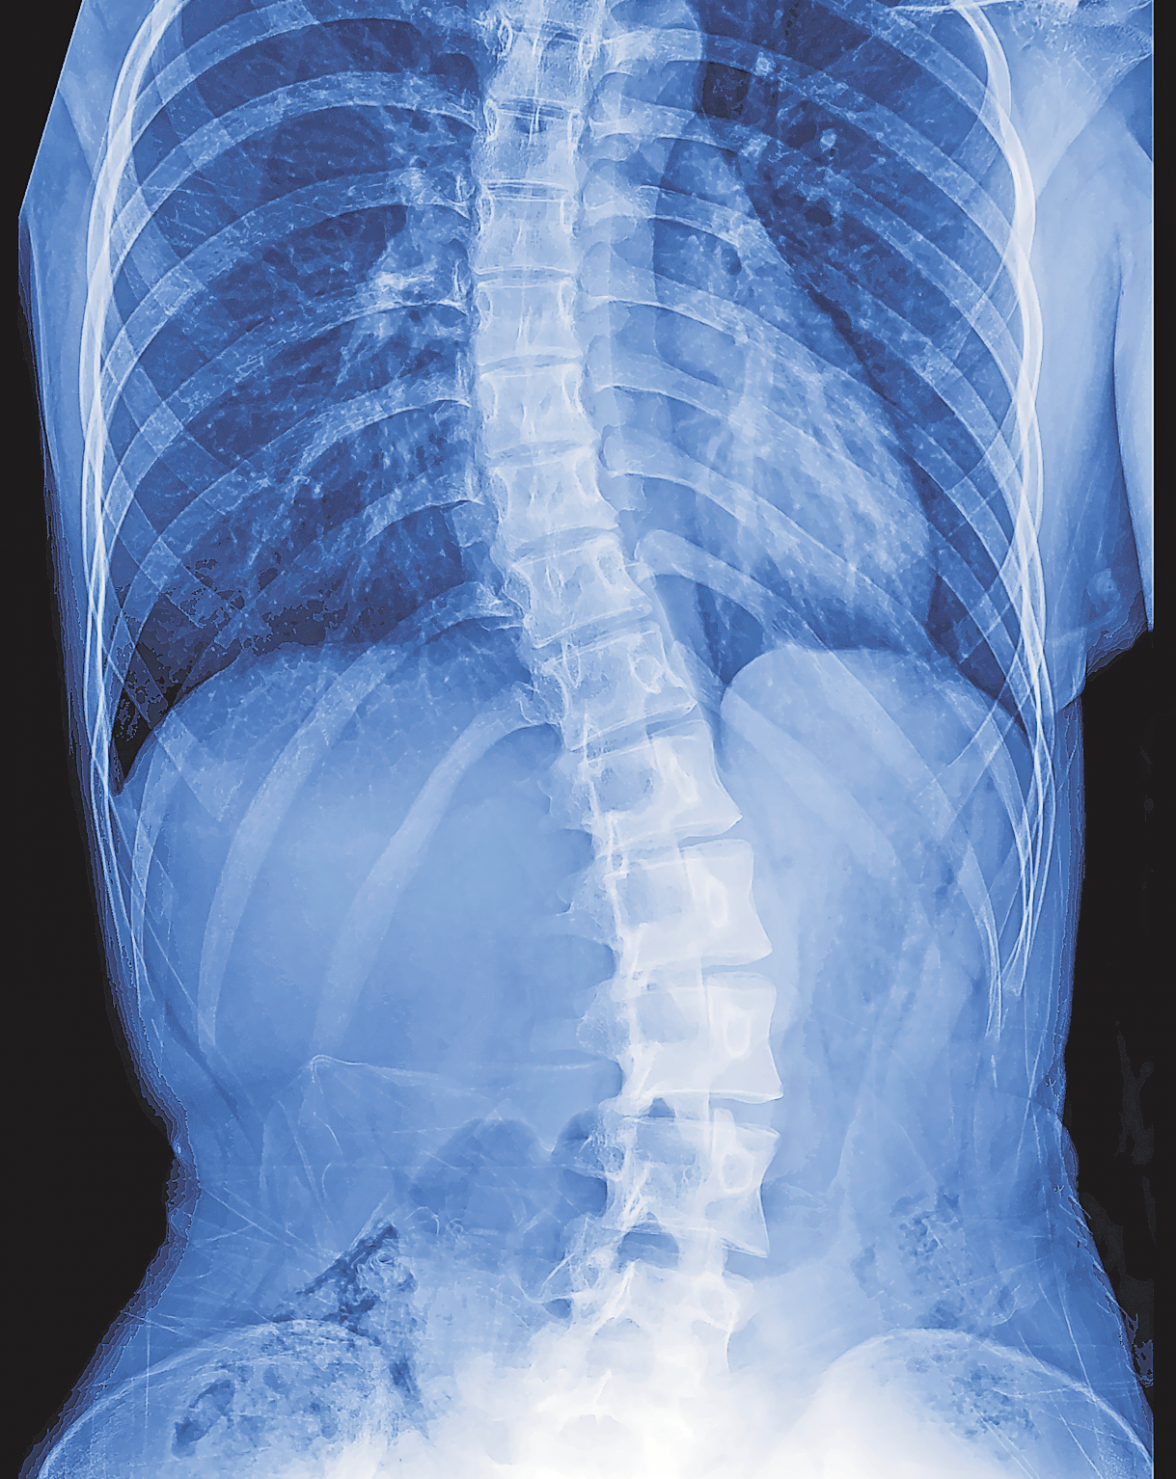

Prinzipiell kann sich an allen Abschnitten der Wirbelsäule eine Skoliose entwickeln, besonders oft ist die Brustwirbelsäule betroffen. Meist weicht dieser Abschnitt zur rechten Seite hin ab, was dann eine Gegenkrümmung der Lendenwirbelsäule nach links zur Folge hat. Aber auch im Lendenwirbelsäulenbereich oder in der Übergangsregion von Brust- und Lendenwirbelsäule kann die Krümmungsmitte liegen. Manchmal weisen sowohl die Brust- als auch die Lendenwirbelsäule einen Hauptkrümmungsbogen auf (Doppel-S-Skoliose). Dabei reichen die Schweregrade von minimalen Verbiegungen, ohne dass gleichzeitig eine Verdrehung (Rotation) der Wirbelkörper besteht, bis hin zu schwersten Formen, bei denen es den Betroffenen nicht mehr möglich ist, aufrecht zu stehen oder ohne Gehhilfe die Balance zu halten.

Physiotherapie, Korsett oder gar OP: Ob eine Behandlung notwendig ist und wenn ja, welche den größtmöglichen Erfolg verspricht, hängt wesentlich vom Grad der Verbiegung ab und davon, wie rasant die Krümmung fortschreitet. Aber auch, welcher Bereich der Wirbelsäule am stärksten betroffen ist (Bestimmung des Scheitelwirbels) und nach welcher Seite die Krümmung der Wirbelsäule zeigt, sind Aspekte, die bei der Therapieplanung berücksichtigt werden. Schwerere Formen der Wirbelsäulenverkrümmung sind zwar äußerlich erkennbar, dennoch lässt sich das genaue Ausmaß einer Skoliose erst mithilfe einer Röntgenuntersuchung erkennen. Das Röntgenbild dient außerdem dazu, den Cobb-Winkel sowie die Skelettreife zu bestimmen. Ergibt die Auswertung eine Verbiegung von mehr als zehn Grad, liegt eine Skoliose vor. Ein grenzwertiger Befund zieht normalerweise erst einmal regelmäßige Kontrolluntersuchungen alle vier bis sechs Monate nach sich, um zu prüfen, ob die Krümmung zunimmt. Ist dies der Fall, wird meist eine speziell für Skoliose entwickelte Physiotherapie verordnet, allen voran die Therapie nach Vojta oder die dreidimensionale Skoliose-Behandlung nach Katharina Schroth. Studien belegen, dass auf diese Weise ein Fortschreiten der Erkrankung deutlich verzögert beziehungsweise im Idealfall sogar aufgehalten werden kann.